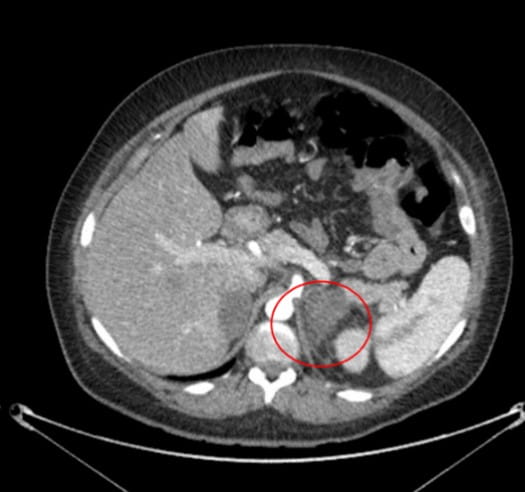

A 30-year-old female with a history of hypertension, cerebral aneurysm, and polycystic kidney disease presented to a UPMC emergency room with nausea and left side abdominal pain during the 31st week of her second pregnancy. An abdominal CT scan showed a 2.3 x 3.1 cm left adrenal hemorrhage (see Image 3).

Image 3: CT without contrast remarkable for enlarged left adrenal gland with adjacent fat stranding. Findings are concerning for left adrenal hemorrhage.